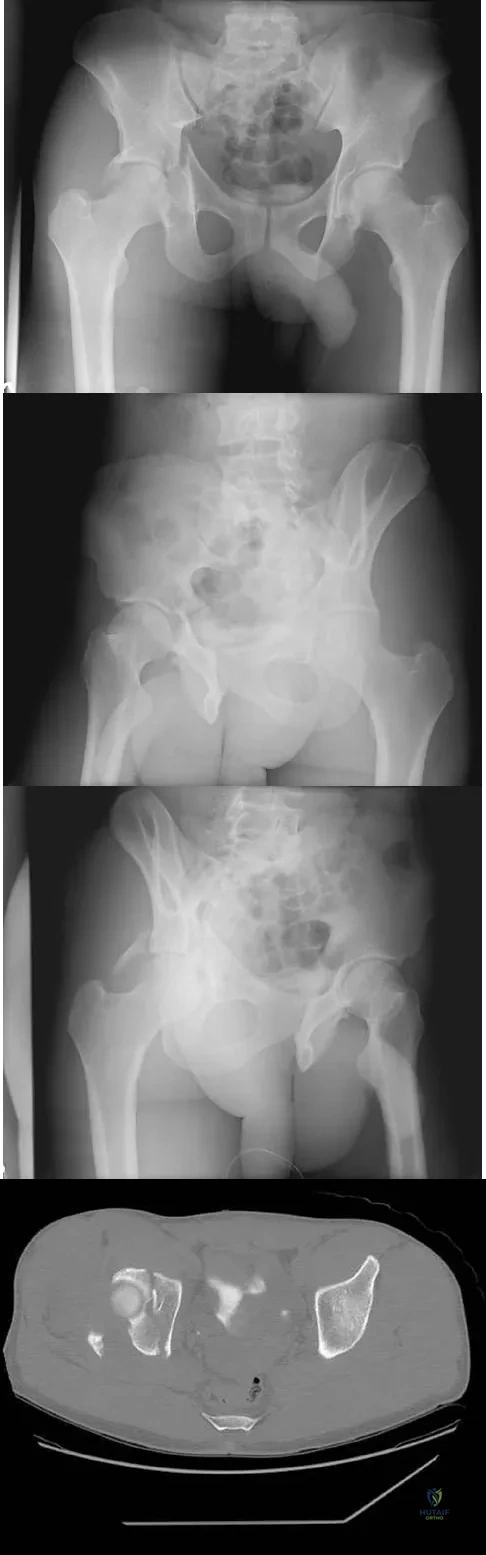

The radiographs and CT scan seen in Figures 28a through 28d reveal what type of acetabular fracture pattern?

Explanation